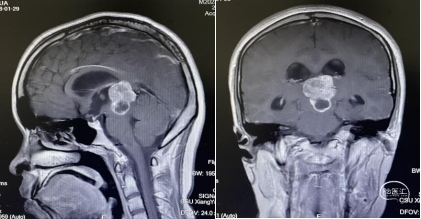

头部磁共振:松果体区可见一稍长-长T1、稍长-长T2信号灶,内可见小片状短丁1信号,增强后实性成分明显不均匀强化,大小约30mmx24mmx33mm,病灶部分伸入第三脑室,第三脑室扩张,双侧丘脑受压移位,中脑导水管,以慕上脑室系统积水扩张,双侧脑室旁可见线样FLAIR高信号。左侧丘脑,左侧脑桥及桥臂可见小片状长T1长T2信号,FLAIR呈高信号。